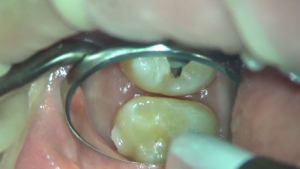

スクリーンショット (22)